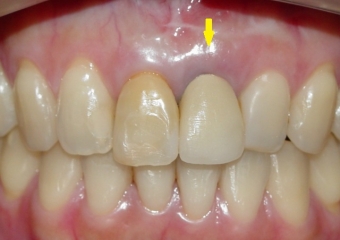

Imagens iniciais com elemento 21 comprometido